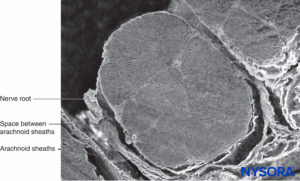

Arachnoid mater consists of two layers, the trabecular arachnoid and arachnoid layers. The trabecular arachnoid merges with the cellular plane of the pia mater and emits projections to all the structures that cross the subarachnoid space, including blood vessels and nerve roots. The projections that cover the nerve roots are called arachnoid sheaths (Figures 32 to 40).

During movement, these sheaths stabilize and prevent excessive movements of the nerve roots within the dural sac. However, the sheaths confer little mechanical protection against trauma. Characteristics of the arachnoid sheaths in the cauda equina are variable; some are lax, while others are formed by superimposed planes of the same components with a more compact appearance. The thickness of an arachnoid sheath ranges from 10 to 60 μm. In some cases, one or more nerve roots are enveloped by a single arachnoid sheath, and in others, the nerve root has no sheath at all.

ARACHNOID SHEATHS OF NERVE ROOTS AND THEIR POTENTIAL ROLE IN NERVE LESIONS

Some cases of cauda equina syndrome and transient neurological syndrome could be explained by the existence of arachnoid sheaths surrounding nerve roots within the dural sac and the fact that needles or (micro)catheters can be inserted into them. An anesthetic solution accidentally injected into the arachnoid sheath of a spinal nerve may not be diluted by surrounding cerebrospinal fluid, thus exposing the nerve root to a higher anesthetic concentration than expected. Consequently, the concentration of the local anesthetic could be magnitudes higher (eg, 20–25 times) in comparison to the concentration of the anesthetic in the rest of the dural sac.

Such high local anesthetic concentration inside the arachnoid sheath could have deleterious effects on nerve roots, as opposed to a typical injection of the same anesthetic solution inside the dural sac but outside the arachnoid sheath. Because it takes time to establish equilibrium inside and outside the sheath, a nerve lesion could develop without direct needle trauma.Injections of local anesthetic through a microcatheter into these arachnoid sheaths could be more devastating than a single injection. This is because the injection of a single large volume would eventually be diluted by leakage outside the sheath, whereas repeated doses of small volumes may be more likely to lead to neurotoxicity due to the continuous or repeated exposure to a high concentration of local anesthetics. Transient root irritation syndrome and cauda equina syndrome may reflect different degrees of nerve damage related to local anesthetic concentration and duration of exposure. Injection of local anesthetic inside arachnoid sheaths in areas close to the spinal cord or to the conus medullaris could affect several nerve roots, while injection in more distal areas may affect single nerve roots.